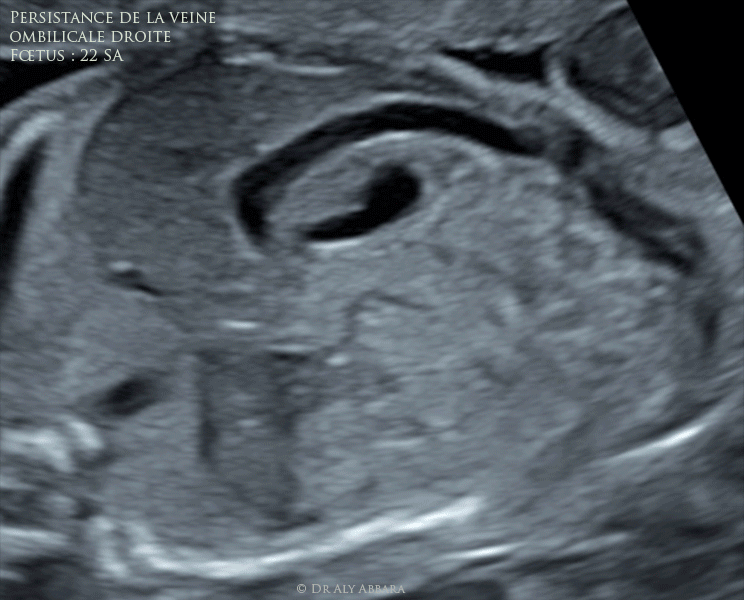

Persistance de la veine ombilicale droite : fœtus de 22 SA

Images échographiques montrant une veine ombilicale droite persistante substituant complètement à la veine ombilicale gauche.

Le parcours de cette veine persistante est intra-hépatique (près de la face inférieure du foie) ; elle se situe à droite de la vésicule biliaire et déplace cette dernière vers la ligne médiane.

Le canal veineux est présent est naissant d'une branche extra-hépatique de cette veine ombilicale droite persistante.

Fœtus de 22 SA ; aucune anomalie morphologique associée.